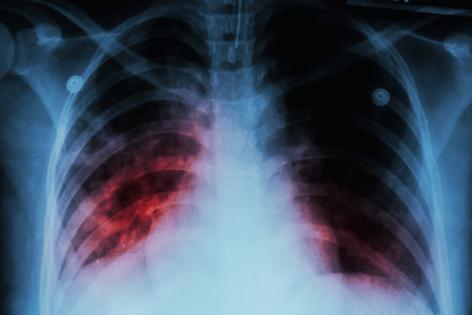

Tuberculosis is an infectious disease caused by bacteria that typically infects the lungs after being spread by coughing, according to the World Health Organization. About 1.2 million people died from TB in 2024 among more than 10 million new infections; roughly one in four people worldwide carries the bacteria without symptoms, while 5–10% develop active disease. Babies and children are at a higher risk of developing the disease if they are infected.

Common symptoms include prolonged coughing, sometimes with blood, chest pain, weakness, fatigue, weight loss, fever and night sweats. The disease is usually treated with antibiotics and can be fatal without treatment.